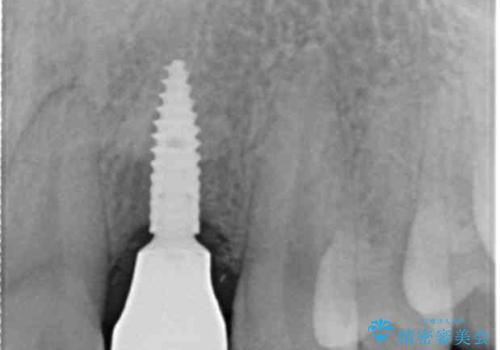

- 55万円(ストローマンインプラント・ジルコニアカスタムアバットメント・骨造成・仮歯・ジルコニアクラウン)費用は治療当時の料金となります

前歯部にインプラントを埋入し、きれいに仕上げるためには骨の造成技術や歯肉の厚みを増すような処置を行い、インプラント周囲の環境を整備することが肝要です。